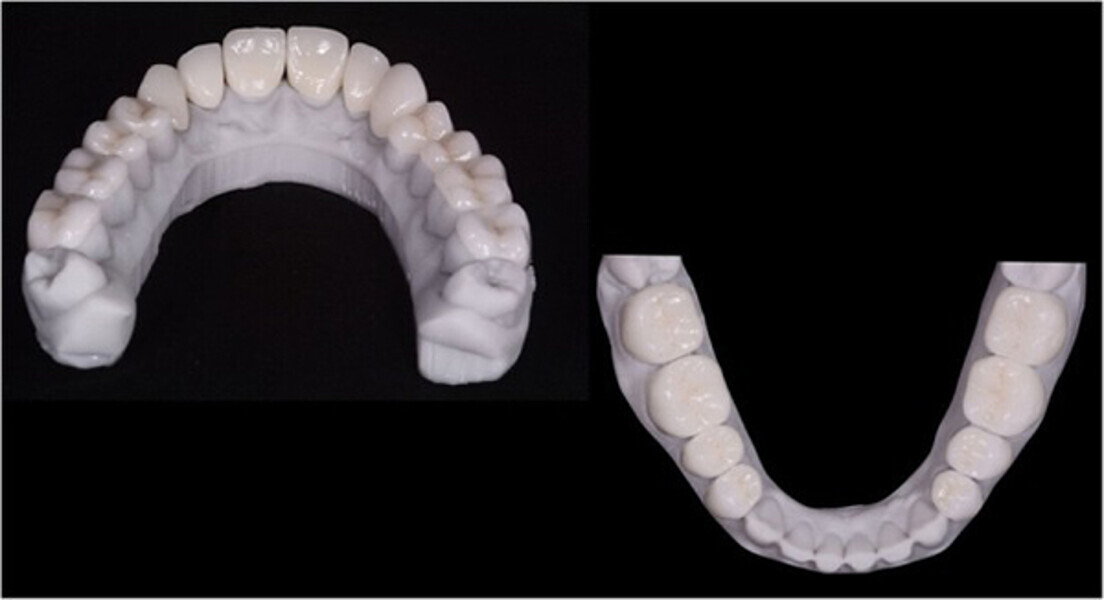

Fig. 12. Carillas y coronas finales preparadas digitalmente con el software de diseño Ceramill Mind y producidas en una fresadora (Ceramill Motion 2) a partir de bloques de cerámica de disilicato de litio mecanizables (VITABLOCS TriLuxe forte).

Fig. 13. Las coronas (#11-13 y 21-23) y las carillas (#14-17, 24-27, 31-37 y 41-47) se cementaron a los pilares utilizando un cemento de resina fotopolimerizable (Futurabond U y Bifix QM).